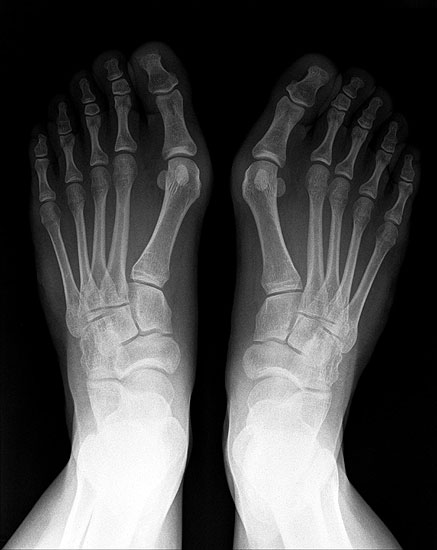

• Hallux valgus interphalangeus (Abb.1, Abb.2)

• Röntgenaufnahme des Fußes (unter Belastung) in dorsoplantarem und seitlichen Strahlengang (Abb. 2a-b).

• Beurteilung des proximalen Gelenkflächenwinkels der Grundphalanx (Proximal Phalangeal Articular Angle, PPAA) sowie des distalen Gelenkflächenwinkels der Grundphalanx (Distal Phalangeal Articular Angle, DPAA) 56 (Abb. 3c und 3d).

• Bestimmung des ersten Intermetatarsalwinkels (IMA, Abb. 3a), des Hallux valgus Winkels (HVA, Abb. 3a), des distalen metatarsalen Gelenskflächenwinkels (Distal Metatarsal Articular Angle, DMAA, Abb. 3b) 7. Möglicherweise muss die Akin-Osteotomie mit weiteren Eingriffen kombiniert werden (z.B.: retrokapitale Osteotomie oder andere metatarsale Osteotomie; Arthrodese).